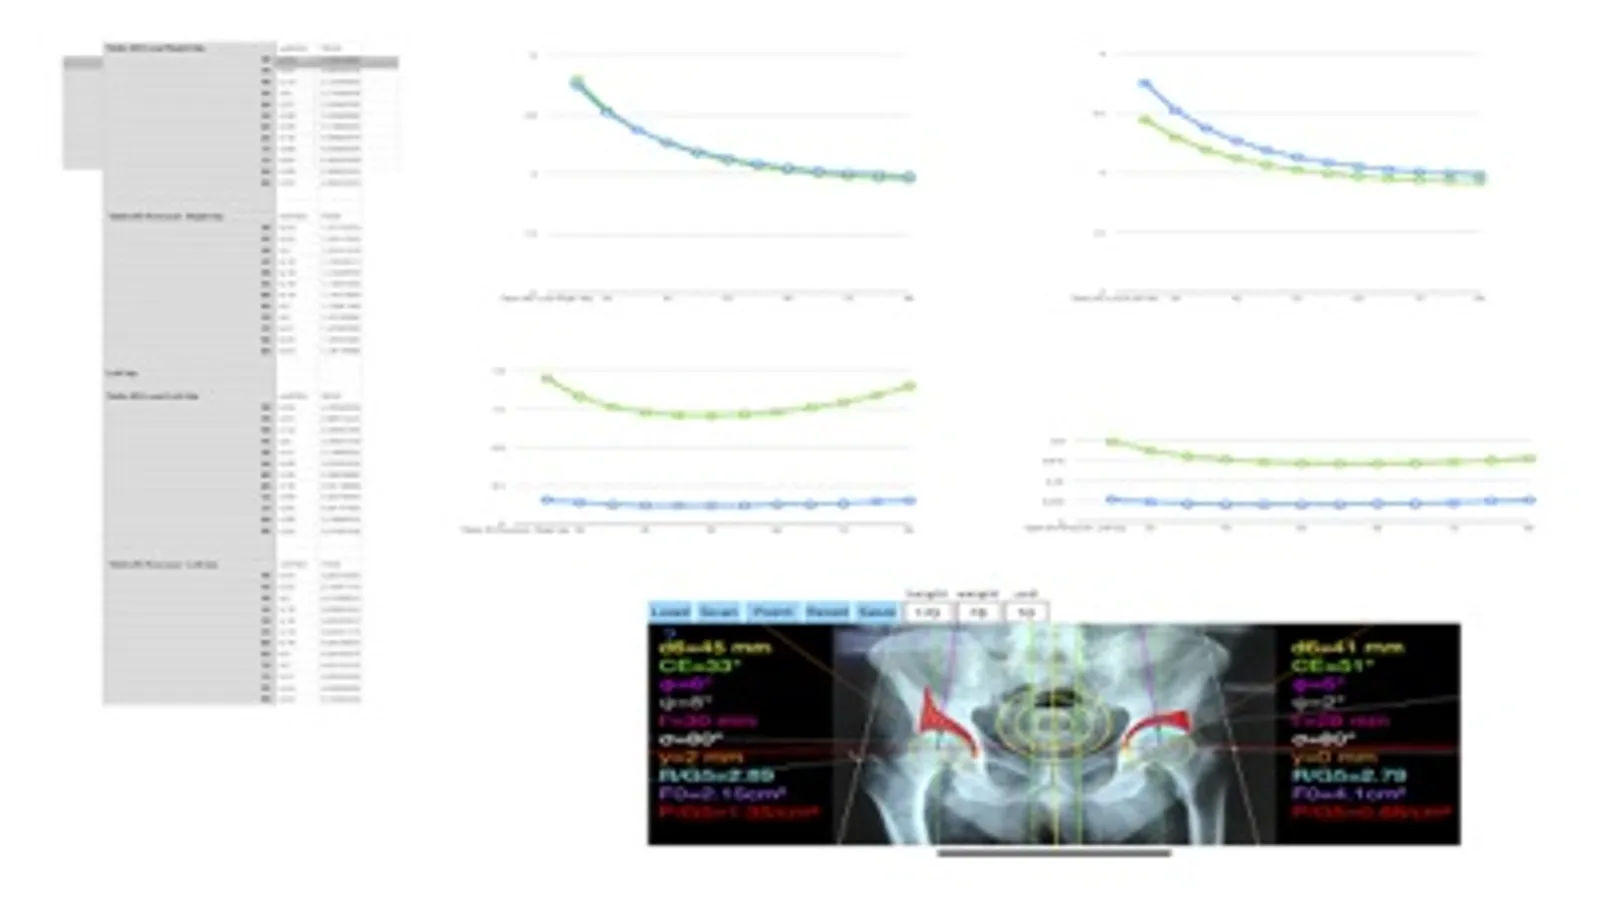

-By marking certain points in a simple standard AP pelvic radiograph, geometric parameters are being calculated. The App computes weight-bearing contact surface, the load (R) and stress (P) on the measured hip.

Data from load and pressure distribution in the hip - like in a real biomechanicals tests- are being measured and depicted graphically as vectors over the X-ray in the screen over the joint. The distribution also of compressive stresses over the acetabulum, which is usually associated radiographic sclerosis over the acetabular margin, are printed in real time over the screen and thus can be easily and objectively evaluated. Besides that, the App provides data in export for diagrams of load (R) pressure (P), which each can be plotted as a curve allowing easy comparison with normal data and thus help decide the orthopaedic surgeon which procedure is objectively indicated.

-The data are printed over to screen so each case can easily assessed

-Save the planned images, for later review or consultation. Data are exported as txt file, ready to print or to input as cells to numbers or excel ready for chart printing and further research.